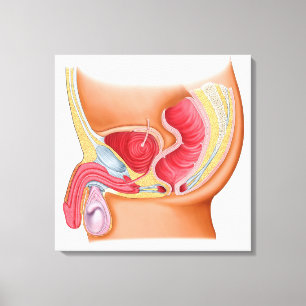

Medicinsk illustration av en Rectourethral Fistula Hälsningskort

Försäljningspris 49,00 kr. Ursprungligt pris 54,00 kr.